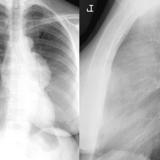

Case 1b

Thymoma